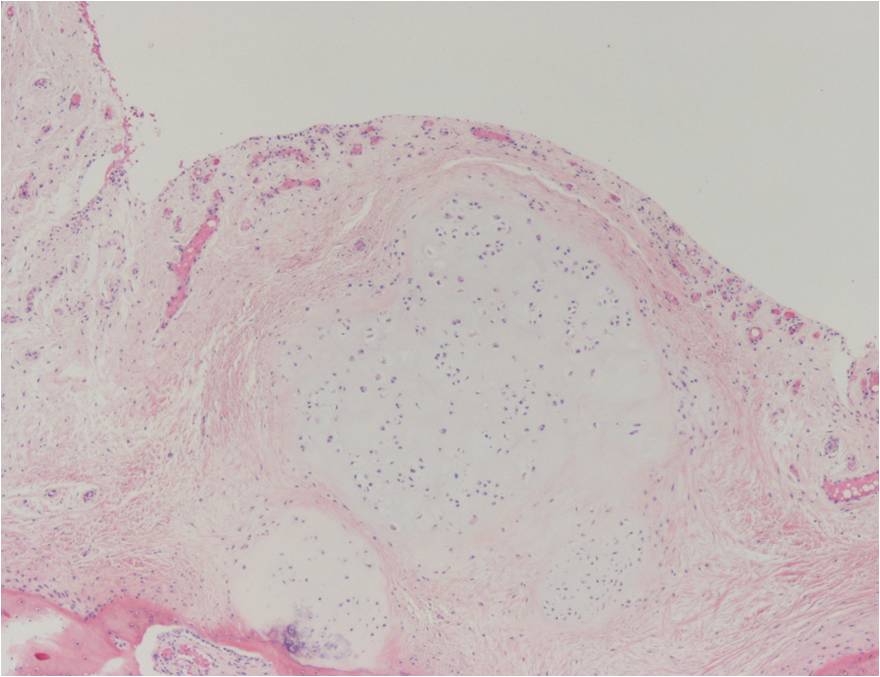

Synovial chondromatosis is an uncommon, benign, process that occurs in large joints, such as the knee (50%), hip, elbow, or shoulder. This process mainly affects synovium and hence most commonly arises from joints and tendons which are lined by synovium. Synovial Chondromatosis may also affect bursae and extend into surrounding soft tissues. This condition is seen in patients between 20 and 50 years of age and most commonly in men (male-female ratio of 2-4/1). The patient usually complains of pain, stiffness, crepitance, swelling, and joint locking. The knee is the most common site to be affected. Symptoms are long-standing and progressive. The plain x-ray may be normal (5 to 33%) or there may be small flecks of calcification (Fig. 1 & 2). On MRI the nodules of cartilage are easily seen. MR imaging may also show synovial thickening, joint erosions and intraarticular calcifications. The signal characteristics of these intraarticular bodies depend of their composition. If mineralization is not present the signal intensity follows the cartilage signal with intermediate signal on T1 images and high signal on T2 weighted MR images. Uniformly calcified bodies follows bone density on all sequences with bone marrow signal centrally and low signal peripherally (Fig. 3-5). Histologically the cartilage is arranged in nodules, which are quite cellular (Fig. 7-9). Synovial lining is present surrounding the cartilage nodules (Fig. 8). The cartilage nodules are often referred to as loose bodies however they are not really loose and embedded in the synovium lining. This is considered a metaplastic condition as opposed to a true neoplastic condition. Rarely it may turn into a malignancy usually a low grade chondrosarcoma. Malignant change is suggested by deep erosions into adjacent bone.

Fig. 7 – 9. Microscopic Pathology. Low (Fig. 7) and intermediate (Fig. 8 & 9) magnification demonstrates nodules of cartilage with high cellularity. Synovial lining is present surrounding the cartilage nodules.